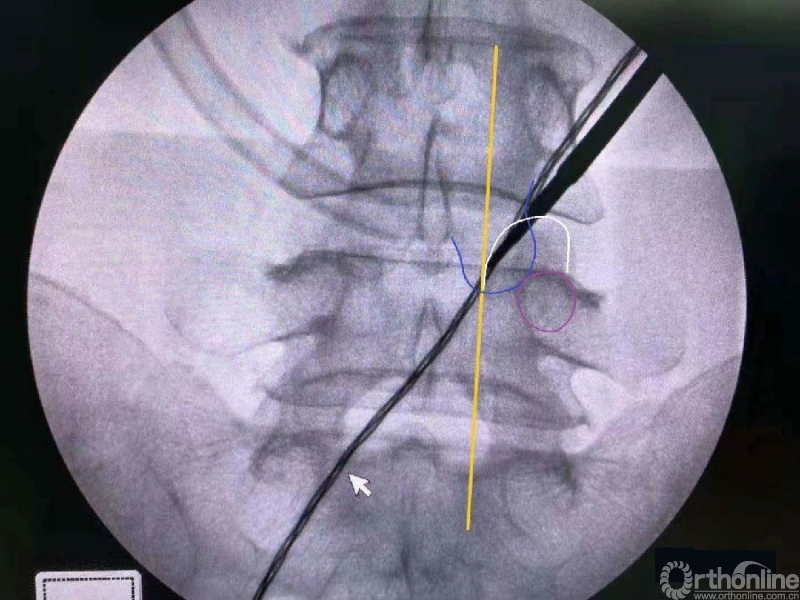

内镜监视下使用mark小磨钻进行第一定位,发现定位线过于偏内。

然后在内镜监视下于第一个孔的外侧进行第二次定位。

第二次定位虽然并位于椎弓根内缘线上,但是我们觉得本病历参考内缘线的话可能会把下关节突的2/3磨掉,所以我们选择第二个接近椎弓根内缘线的定位孔作为镜下下关节突内缘切除的外界。

术中第一次及第二次的两个定位孔